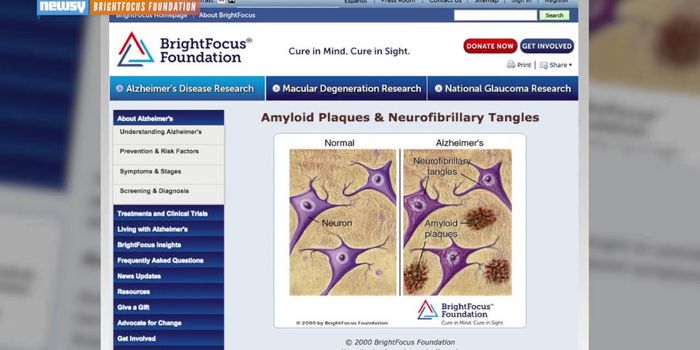

NOV 13, 2017InfographicsIn 1983, President Ronald Reagan designated November as National Alzheimer’s Disease Awareness Month. As it turns ...